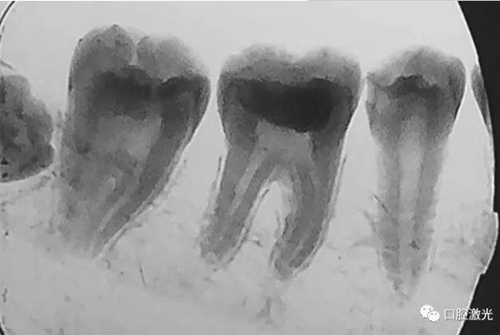

活髓理療治療結(jié)果令人滿意,沒有出血,也沒有出現(xiàn)碳化。患者沒有感受到不適并表示滿意。為了跟蹤激光輔助活髓切除術(shù)的治療效果,手術(shù)完成即刻和5周后分別拍攝了X光圖像。5周后的牙髓活性溫度測(cè)試也顯示陽性。

治療后5周